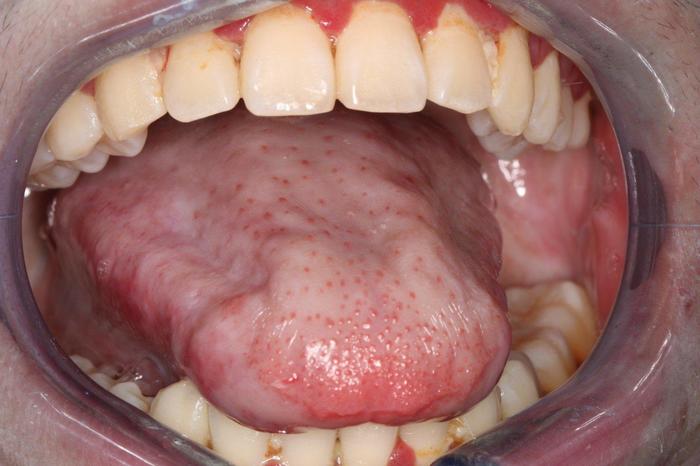

口腔内黏膜炎黏膜炎症是化疗或放疗的副作用之一,严重的情况下可能会